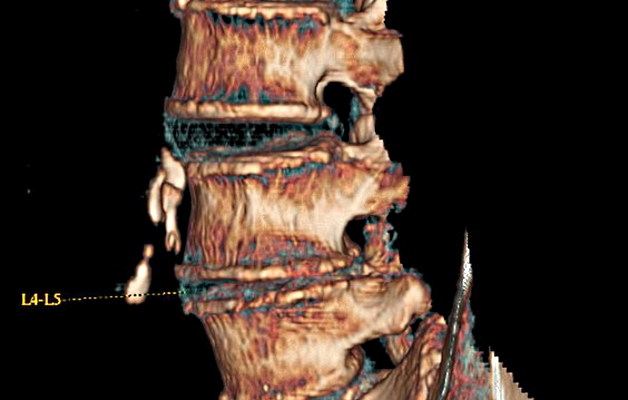

Чтобы уточнить диагноз, после беседы, визуального и пальпаторного обследования больного отправляют на аппаратную диагностику:

- Рентгенографию – показывает присутствие и размер остеофитов, изменение плотности кости тел позвонков, размер щели между телами позвонков (местонахождение межпозвонкового диска), клювообразное срастание остеофитов (спондилез на фоне остеохондроза).

- Компьютерную томографию – показывает просвет спинномозгового канала, грыжи, врожденные аномалии, состояние сосудов и мягких тканей.